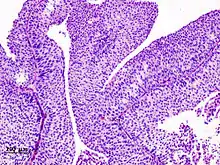

![]() | Tuberculoid leprosy | Skin biopsy showing multiple peri-appendageal granulomas. | Category: Histopathology of leprosy | Leprosy |